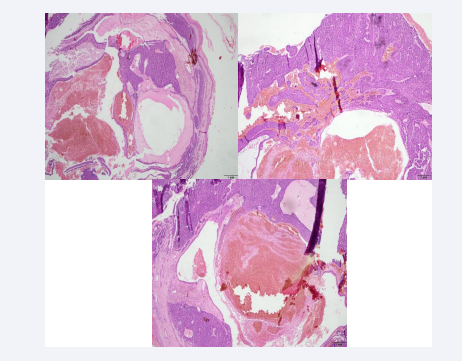

In the first instance, in June 2021, a biopsy is requested which determines (Figures 1-3) that there are neoformations consisting of two histological patterns and finally it is concluded that they are treated as ´´Multiple Spiroadenocylindromas´´ type lesions.

Figure 1: The sections show atrophic skin with loss of the ridge network that surrounds a neoformation consisting of two different histological patterns. The first and predominant one is composed of a multinodular proliferation composed of small cells with round and hyperchromatic nuclei and larger cells with clear cytoplasm, vesicular nucleus and prominent eosinophilic nucleolus, which are arranged in a trabecular pattern, with foci of ductal differentiation. presence of hyaline droplets and predominantly lymphocytic inflammatory infiltrate. Courtesy: Dr. Mónica Salazar- Dermatopathologist

Figure 2: A second pattern is composed of islands of basaloid cells that have a puzzle-shaped arrangement and are surrounded by a thickened eosinophilic basement membrane. In addition, prominent cystic changes are observed that compromise the spiradenomatous part of the lesion and are associated with intratumoral hemorrhage. Courtesy: Dr. Mónica Salazar- Dermatopathologist